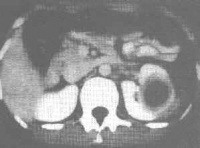

肾脓肿

肾脓肿(renal abscess)

肾脓肿是指肾脏实质因炎症化脓而被破坏,形成一脓性包囊,肾功能完全丧失,常见于上尿路梗阻的患者。